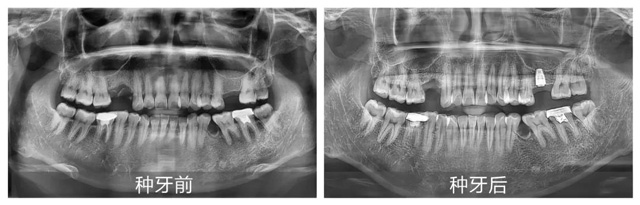

为提升缺牙市民对种植牙手术安全性和可靠性的认知,缓解公众对手术过程的恐惧和疑虑,12月19日,“种牙真功夫”数字化种植牙手术直播第十九期在新桥口腔成都光华院区精彩上演,活动全程直播,邀请顾客零距离感受种牙全过程,共同见证缺牙重生。

“数字化种植是新桥口腔的优势项目,无论是单颗还是全口牙种植,我们都会依据患者的口腔状况进行一对一3D数字化种植方案制定,通过使用数字化CBCT影像、3D口扫等完成术前一站式检查,有效规避后续治疗中可能存在的风险与误差。”针对今天种植直播的案例,李丹主任讲到:“我们在术前评估发现患者上颌骨量非常有限,骨高度仅为7毫米,而常规种植体至少需要8毫米的高度才能确保安全植入,为了避免可能出现的损伤,谢医生在种植手术中还需要再做一个专业、严谨的上颌窦提升手术。”

在李丹主任详细讲解的同时,手术室也已准备就绪,观众们通过实时投影,近距离见证了种植牙手术的过程。从术前消毒到定量麻醉,从精准植入再到严密缝合,谢海洋医生有条不紊地完成了每一个关键步骤,整个手术过程高效流畅。